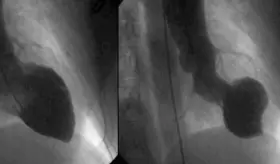

#MSPCardiología | ¡Ahora! El Bayamón Heart & Lung Institute realiza y transmite en vivo una cirugía desde la Isla hacia CTO Plus 2026, liderada por el Dr. Ricardo Santiago, cardiólogo intervencional. ¡Sintonízanos ahora y no te pierdas ningún detalle!

Desde el Bayamón Heart and Lung Institute, se ofrecen intervenciones coronarias complejas y de alto riesgo para pacientes con bypass previos, stents obstruidos, oclusiones totales crónicas y anatomías difíciles.

El IVUS permite visualizar detalles de las arterias, crucial para intervenciones complejas como bifurcaciones o restenosis.